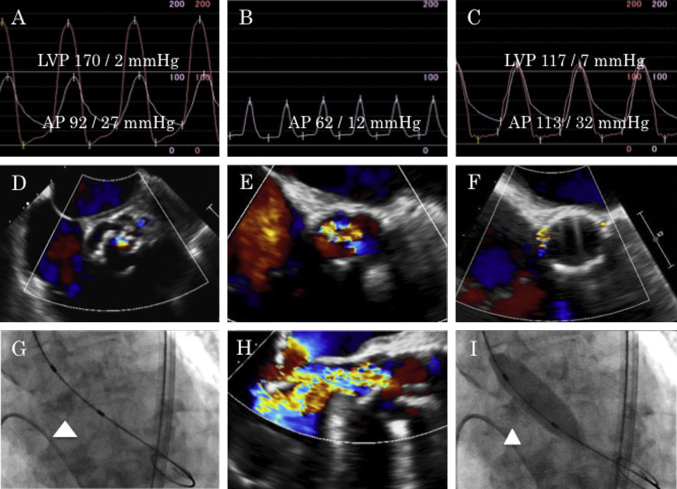

Fig. 2.

(A) Pre-procedural simultaneous aorta and left ventricle pressure curves. (B) Aortic pressure during severe acute aortic regurgitation. (C) Simultaneous aorta and left ventricle pressure curves after valve implantation. (D) Mild aortic regurgitation before percutaneous transluminal aortic valvuloplasty (PTAV). (E, H) Severe acute aortic regurgitation through the non-coronary cusp after PTAV. (F) Trivial peri-valvular leakage after salvage transcatheter aortic valve implantation. (G) Bulky calcification of non-coronary cusp (arrowhead). (I) Balloon aortic valvuloplasty and entrapment of the calcified non-coronary cusp (arrowhead). LVP: left ventricle pressure, AP: aorta pressure.

We performed PTAV under local anesthesia by a retrograde approach from the right common femoral artery. We inserted a 12-French long sheath into the right common femoral artery and placed a stiff wire in the left ventricle apex. Pressure gradient between the left ventricle and ascending aorta (peak to peak) was 78 mmHg (Fig. 2A). We chose a 16-mm balloon based on prior test results and expanded it under rapid ventricular pacing. After the first expansion, hemodynamics suddenly deteriorated and diastolic blood pressure fell to 12 mmHg (Fig. 2B). Echocardiography detected severe AR from the non-coronary cusp (NCC), which was not found before the procedure (Fig. 2E and H). Although echocardiography could not reveal cusp itself, cineangiography showed balloon inflation had entrapped the calcified, bulky NCC in an open (erect) position, and failure of the NCC to close had led to severe AR (Fig. 2G and I). We attempted to reposition the NCC using an 8-French JR guiding catheter, but failed. For life-saving purposes, we converted the procedure to salvage TAVI immediately after obtaining consent from the family.

We replaced the 12-French long sheath with a 16-French e-Sheath (Edwards Lifesciences, Irvine, CA, USA). Under rapid ventricular pacing of 190 per minute, we deployed a 23-mm Edwards SAPIEN XT valve with 3 ml underfilling (Edwards Lifesciences) (Fig. 2C). No significant peri-valvular leakage (Fig. 2F), annulus rupture, coronary obstruction, and aortic dissection were detected. Echocardiography revealed good function of the prosthetic heart valve (effective orifice area, 1.6 cm2; maximum velocity, 2.0 m/s; mean pressure gradient, 7.9 mmHg). Right bundle branch block that had existed before PTAV progressed to complete atrio-ventricular block after valve deployment. Because her iliac arteries were at the lower limit of the recommended vessel diameter and had atherosclerotic changes, the right external iliac artery was ruptured. We surgically replaced the right external iliac artery via a retroperitoneal approach.